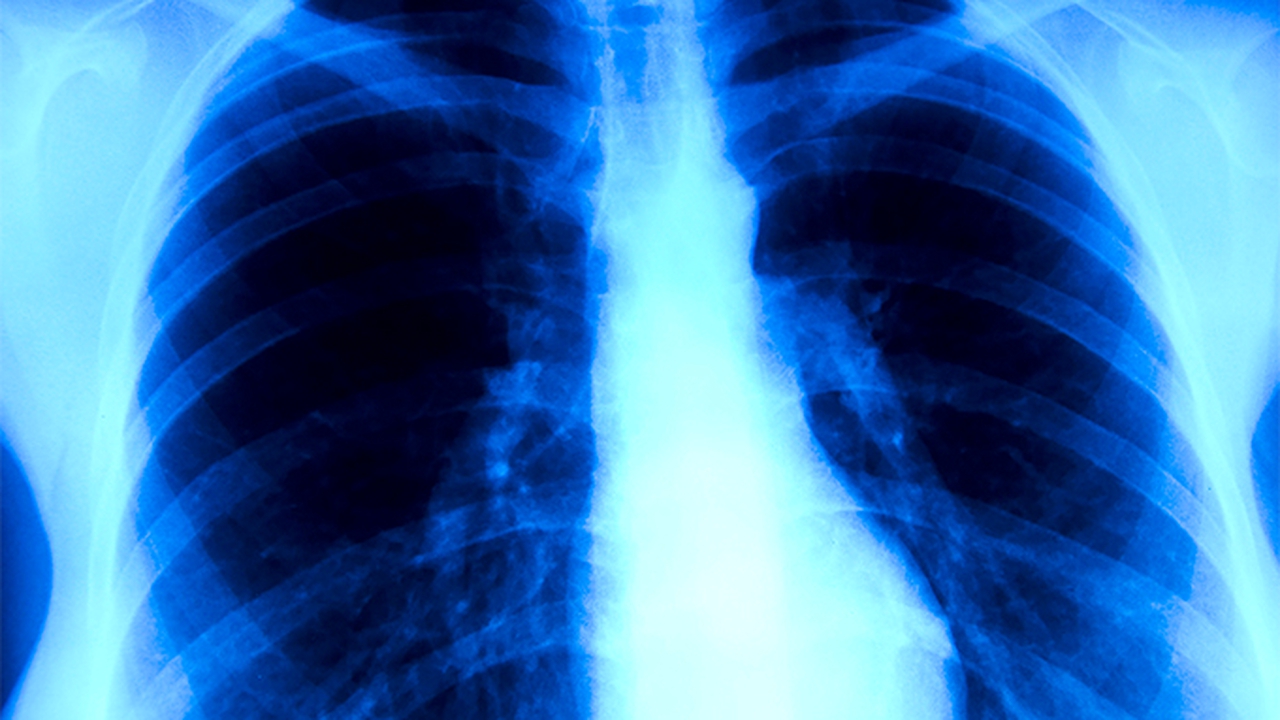

无症状感染者肺部cT正常吗

无症状感染者肺部CT检查结果通常是正常的。无症状感染者是指感染病原体后未出现明显临床症状的人群,其肺部CT检查多数情况下不会显示异常影像学改变。

无症状感染者虽然携带病原体,但病原体可能尚未对肺部组织造成实质性损伤,或机体免疫系统有效控制了病原体的复制与扩散。这类人群的肺部组织结构完整,肺泡通气功能正常,CT扫描通常表现为双肺纹理清晰、无磨玻璃影、无实变影、无结节或肿块等异常征象。部分无症状感染者可能出现轻微的支气管壁增厚或小叶间隔增厚,但这类改变多属于可逆性炎症反应,随着病原体清除可自行恢复。

极少数无症状感染者可能因个体差异、免疫状态特殊或合并潜在肺部疾病,在CT检查中出现局限性磨玻璃样改变、微小结节等轻微异常表现。这些改变通常范围较小且密度较淡,与典型肺炎的弥漫性病变存在显著区别。此类情况需结合病原学检测、炎症指标及动态影像学复查综合判断,不能单独作为疾病活动性的依据。